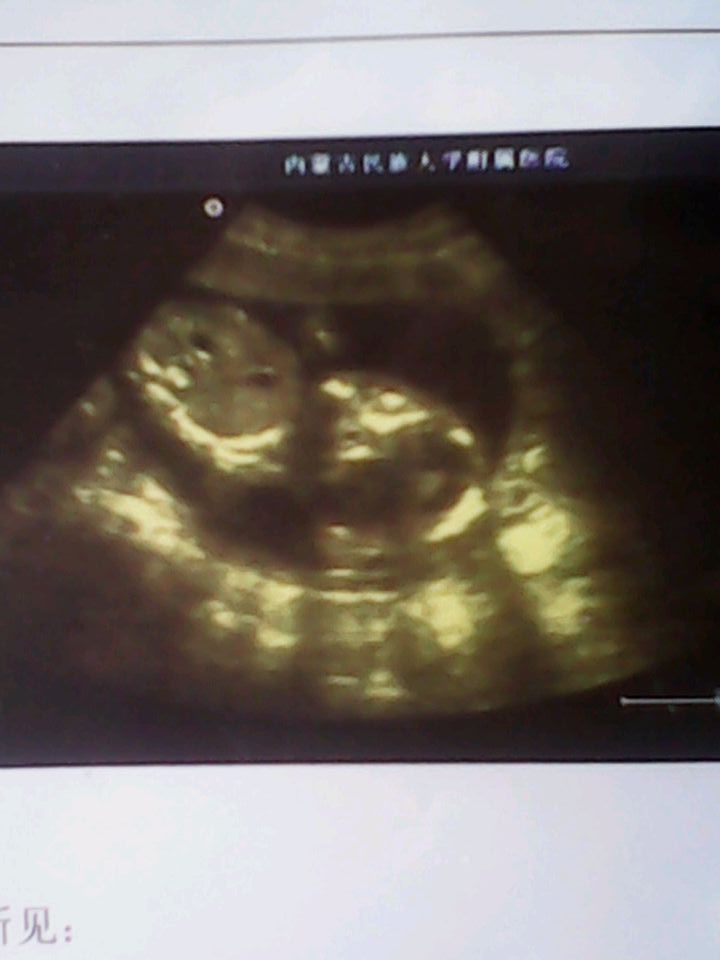

超声所见,子宫增大 宫内见一胎儿影响 胎头双顶径4.0cm 头围13cm 脑中线居中 颅骨完整 脊柱连续 腹围11cm 股骨长2.9cm 胎心154次/分 胎动正常 胎盘位于子宫后壁 羊水最大深度7.2cm怀孕四个多月了